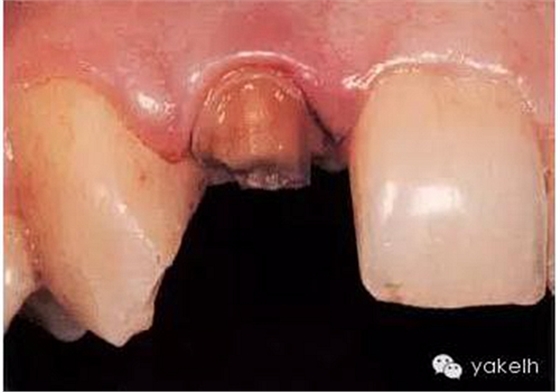

¤¤最終,患者同意12根管再治療后樁核冠修復(fù)。臨床上,應(yīng)在拆除現(xiàn)有修復(fù)體、評估冠部剩余牙體量后,方能確定最終治療方案(圖6.3.2)。

圖6.3.2 拆除12現(xiàn)有修復(fù)體后剩余的牙體組織。